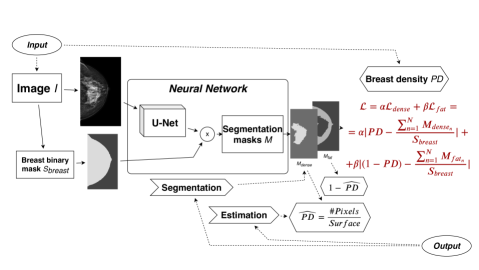

In clinical practice, breast density is usually assessed image-wise using a classification grid like the BI-RADS (Breast imaging-reporting and data system) [Irshad et al.(2016)Irshad, Leddy, Ackerman, Cluver, Pavic, Abid, and Lewis]. In the present work, we propose to estimate breast density at the pixel level while using only image-wise ground truth from the BI-RADS scale. Our goal is to generate a breast density mask, identifying pixels associated with the tissue that contributed to the density class. To achieve our goal, we propose a novel loss linking the sought breast density mask to the globally estimated breast density (fig. LABEL:fig:architecture). We formulate the problem as a weakly supervised binary semantic segmentation. Our approach is related to recent efforts to reduce the amount of supervision [Carneiro et al.(2017)Carneiro, Peng, Bayer, and Navab, Dubost et al.(2017)Dubost, Bortsova, Adams, Ikram, Niessen, Vernooij, and De Bruijne].

In practice, we rely on a modified U-Net architecture [Ronneberger et al.(2015)Ronneberger, Fischer, and Brox] and on an extended 12-class density grid that improves the density resolution compared to traditional BI-RADS classification (4th edition). Compared to the state-of-the-art, our classification and segmentation scheme does not rely on the modelfls attention but uses a loss function efficiently correlating a tissue mask with the target breast density values. Moreover, the output is constrained with the breast binary mask removing useless activations.

fig:architecture